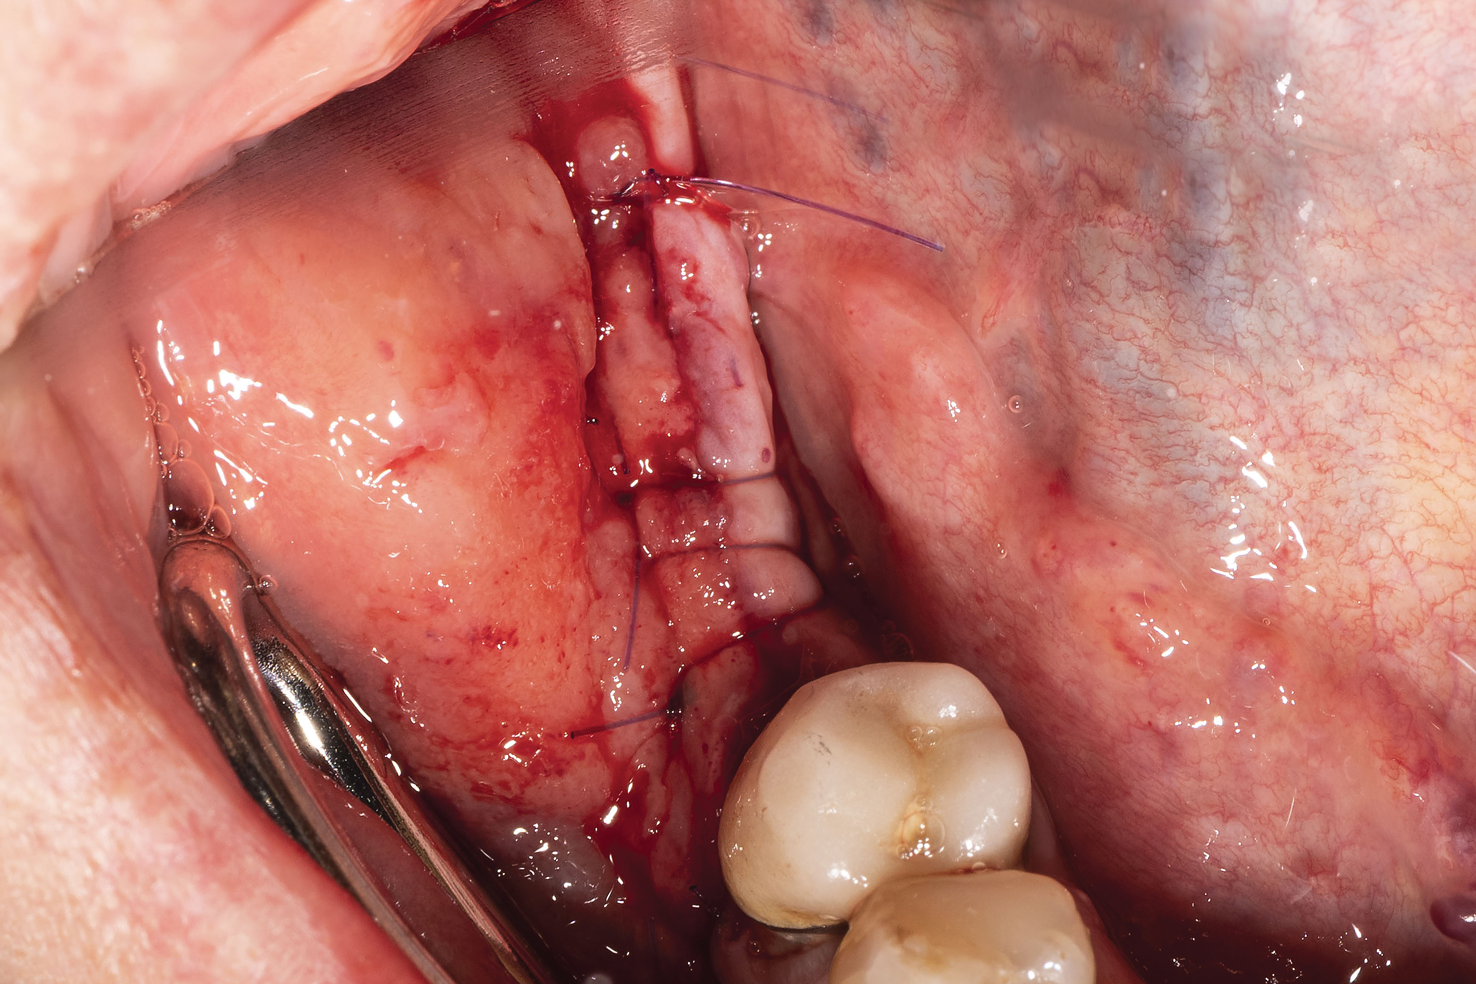

Fig 3. Premolar extracted and flap release.

Figure 3

Patient 1 was a 69-year-old man who was a former professional athlete. He developed heart issues, which led to the use of various medications, such as metoprolol, Ventolin, Seretide, pantoprazole, Rhinocort, and Eliquis. Based on a CBCT scan (Figure 1), the patient needed augmentation in the mandibular left jaw (Siebert class I). Radiographic examination revealed a periapical lesion present at site No. 20 as well as a very thin ridge width of only 3.7 mm in the posterior mandible. Implant planning was performed using planning software, and a custom-made titanium mesh was designed (Figure 2).12

The patient received amoxicillin 500 mg 3 times a day for 10 days, starting the day before surgery.13,14 A full-thickness flap was elevated, extending from tooth No. 22 to at least one tooth mesial and distal to the mesh placement area (Figure 3). Although a vertical releasing incision was not necessary mesially, one can be made to allow sufficient tissue and ensure tension-free closure. It is important that the vertical incision does not end at the joint between the host bone and mesh. The periosteum in this case was left intact and no superficial release of the mylohyoid lingual was necessary.3,15,16